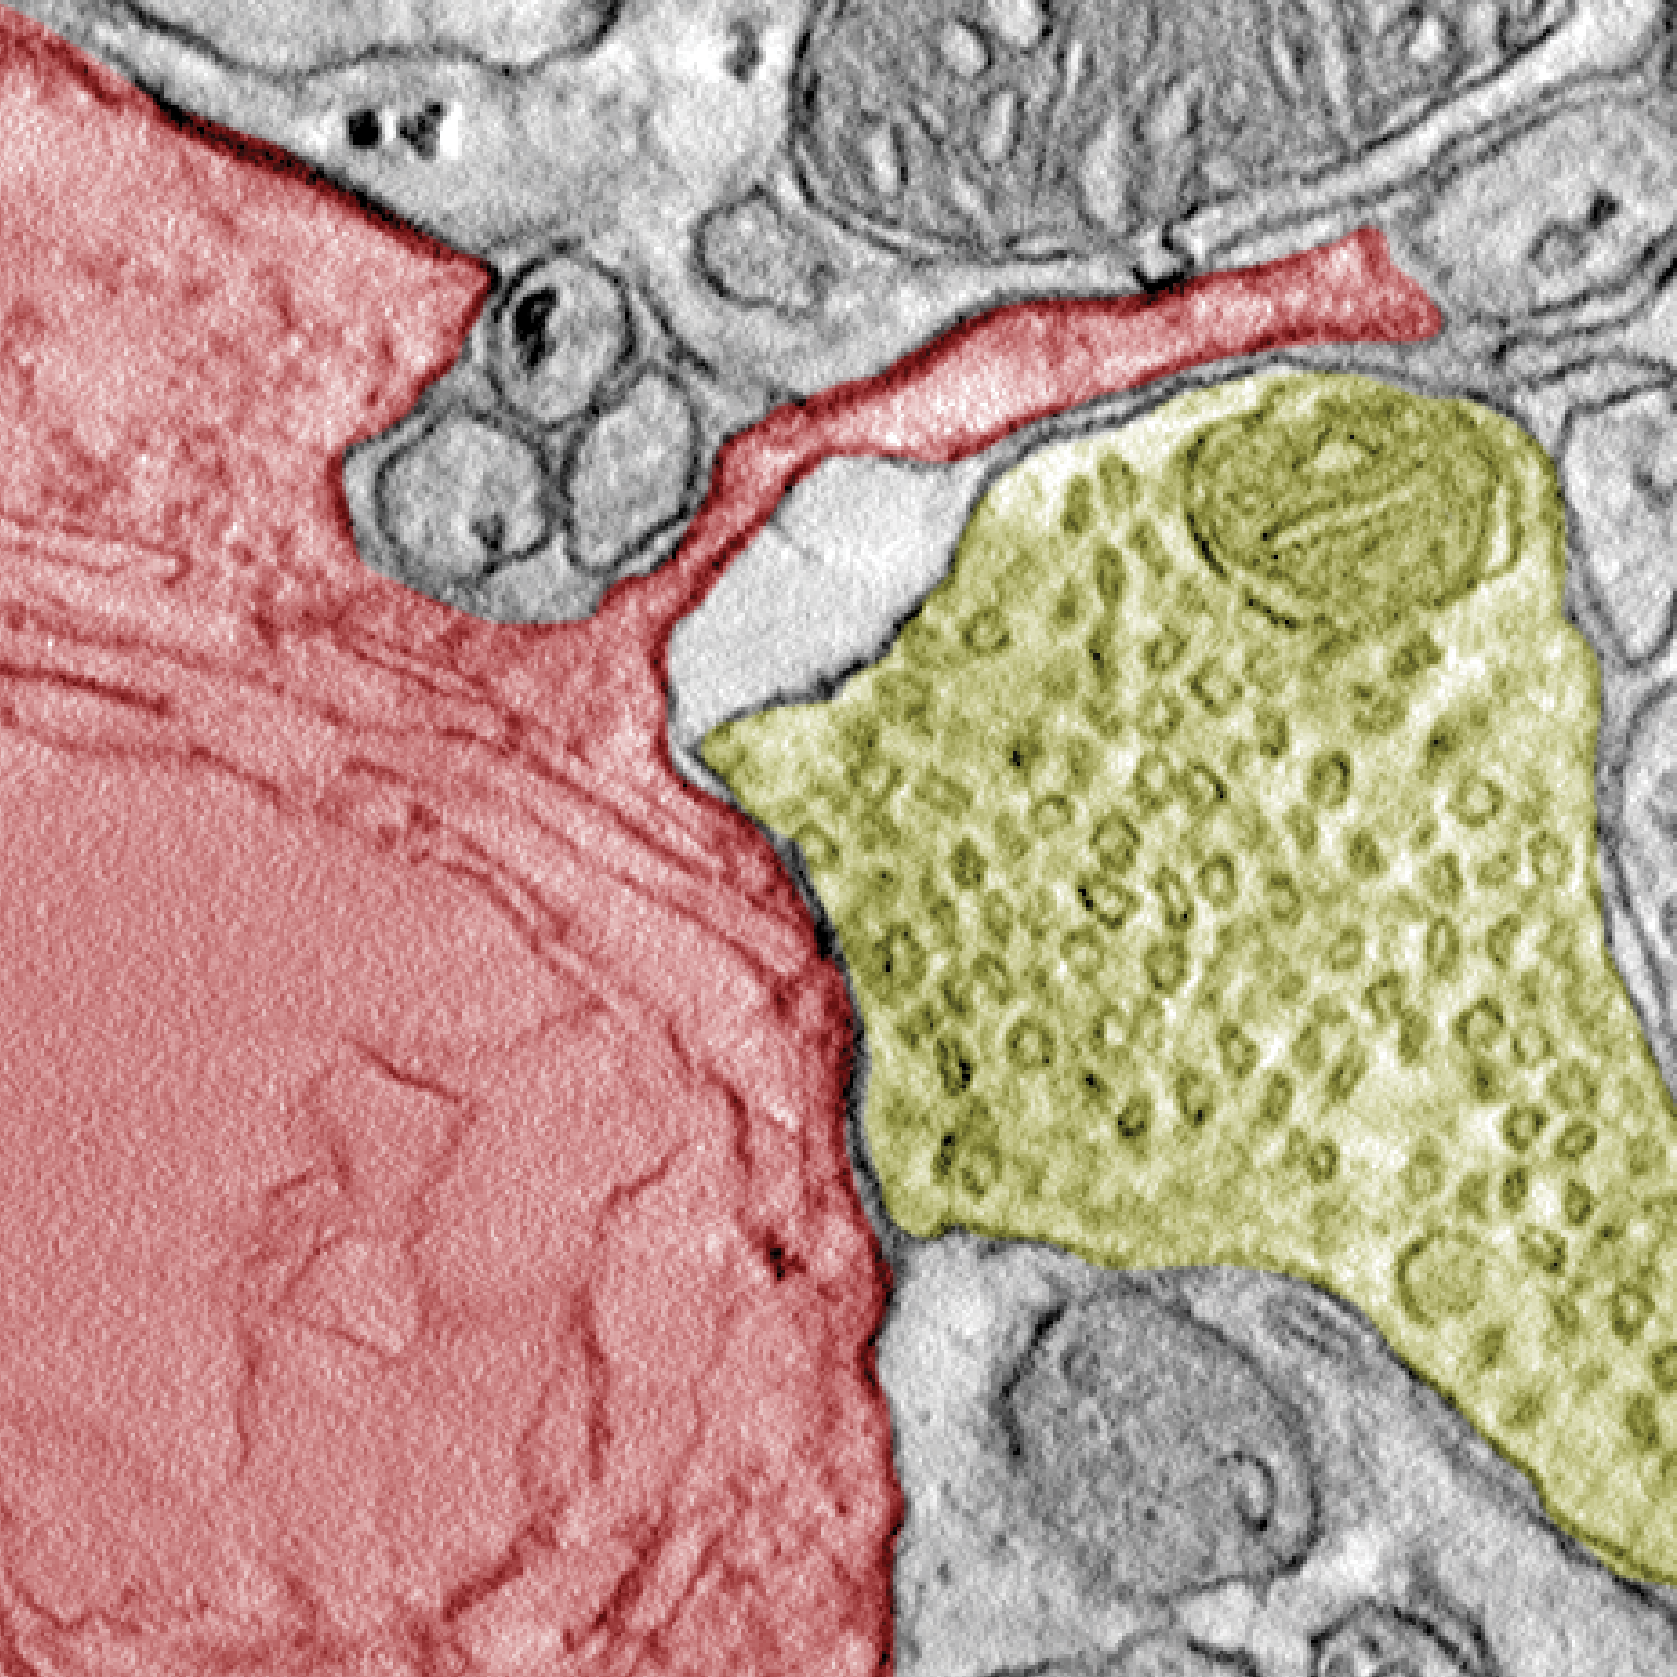

🚨 Cancer cells hijack neural networks: Researchers uncover new dimension of cancer biology 🧠

An international research team lead by Dr Filippo Beleggia has discovered that small-cell lung cancer cells form functional synapses with neurons to grow faster.💡

💊The study titled “Functional synapses between neurons and small-cell lung cancer” was published in Nature nature.com/articles/s41586-025

Elektronenmikroskopische Aufnahme von einer Krebszelle (rot) und einer Nervenzelle (gelb).